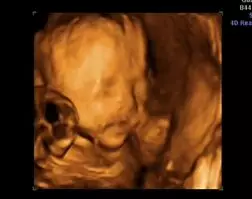

此时主要进行胎儿系统超声或是四维超声,但是最佳时间是孕23~25周。这个阶段的超声检查在是最重要的,四维超声能够很好对胎儿体表进行系统检查,以便筛查产前胎儿的畸形,例如唇裂、脊柱裂、大脑、肾脏、心脏、骨骼发育不良等,以便尽早进行治疗。